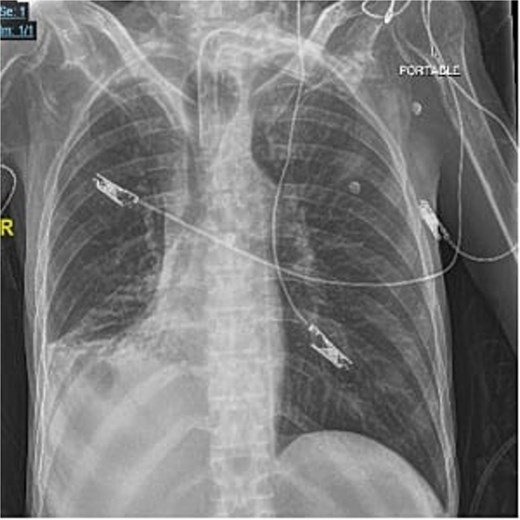

A 40-year-old male who is known to have amyotrophic lateral sclerosis was admitted to the intensive care unit for ventilatory support. He underwent surgical tracheostomy for long-term mechanical ventilation dependence, a double-lumen tracheostomy tube with an internal diameter of 8 mm and a maximum cuff pressure of 25.4 mm was inserted, post-operative chest X-ray confirmed tube placement (Fig. 1). Six months later, the otolaryngologist on-call was consulted regarding ventilation leak that was evident in the ventilator. Flexible endoscopy through the stoma revealed a significantly dilated trachea with a posterior groove. The tube was changed to size 7 with an extended distal length of 49 mm to bypass the dilated segment. A temporary improvement was noted; however, the leak was noted again, with an inspiratory tidal volume of 800, and an expiratory volume of 135, the cuff pressure was gradually elevated to overcome the leak reaching a maximum of 40 mmHg, with the cuff seen over-inflated in routine supine chest X-ray (Fig. 2). Multiple tube obstruction events happened later, which required rigid bronchoscopy examination under general anesthesia to assess and relieve the obstruction. Intraoperative examination revealed that the obstruction was caused by a large dry blood clot, withdrawal of the tube to examine the trachea further revealed a large posterior tracheal wall defect with exposed thoracic vertebrae. The patient underwent a subsequent contrast-enhanced computed tomography scan (CECT) of the neck and chest which confirmed the intraoperative findings (Fig. 3). The leak was not improving by increasing cuff pressure, consequently, the decision was made to use an armored endotracheal tube size 8 at a lip level of 13 to bypass the defect. This has slightly improved the oxygenation and ventilation of the patient, but it did not eliminate the leak. The general poor health of the patient along with his do-not-resuscitate (DNR) status has led to deterring the decision of surgical tracheal wall repair. The patient was further diagnosed with sepsis due to multiple infection sources including his long-term suprapubic urinary catheter, he eventually had a cardiopulmonary collapse a few weeks later and passed away.

Frontal portable chest radiograph showing a tracheostomy tube in satisfactory position above the carina, however, there is a rounded radiolucency at the expected position of the tracheostomy cuff suggestive of tracheostomy tube cuff overinflation. Additionally, there is a small right pleural effusion with adjacent atelectatic changes/ consolidation.